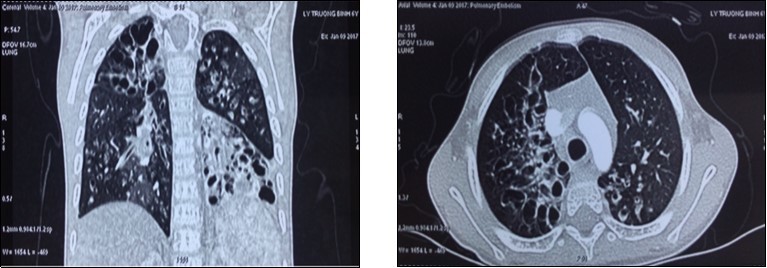

A 7 years old boy was diagnosed of difuse congenital bronchiectasis with chronic respiratory failure and cor pulmonale. At the age of 2 months, he had many respiratory infections. When he was 2 years old, respiratory infection became more frequently, he has been usually hospitalized due to uncontrolled recurent respiratory infection. His main complains were frequent cough with sputum and shortness of breath. On September 2016 patient hospitalized with fever, cough with sputum purulence, severe dyspnea (mMRC of 4 points), cyanosis, difuse crackles in the both lungs, and severe malnutrition (height: 90 cm, weight: 11 kg, BMI: 13.5). The subclinical tests: PaO2: 77 mmHg, PaCO2: 46 mmHg, pH 7.46, SaO2 95% and HCO3-26.7mmol/l. CT-scan: severe difuse bronchiectasis; ECG: sinus tachycardia, right atrial hypertrophy; echocardiography: right ventricle enlargment, pulmonary arterial hypertension (47 mmHg). Blood group: O (+), Rh (D) (+); HLA class I: A02; A24; B13, B52; HLA class II: DRB1 01; DRB1 14. (Image 1)

Image 1.The chest CT-scan image of receipient (difuse bronchiectasis)